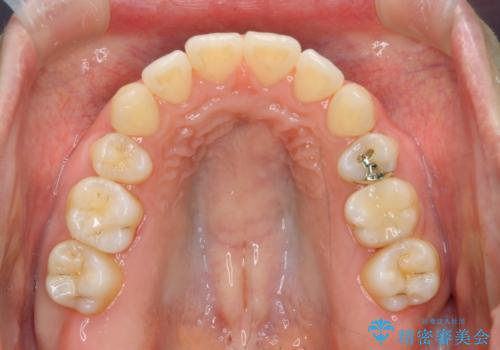

再矯正 昔ワイヤーで治療 前歯の並びを再度きれいに

- 小さいころに小臼歯を抜歯しワイヤー矯正をしたが、すき間が空いてきて、前歯の並びが戻ってしまったとのこと。

インビザラインライトという部分矯正コースで、全体矯正に比べ、比較的安価に治療しました。

前歯の並びが格段にきれいになり、大変喜んでいただけました。